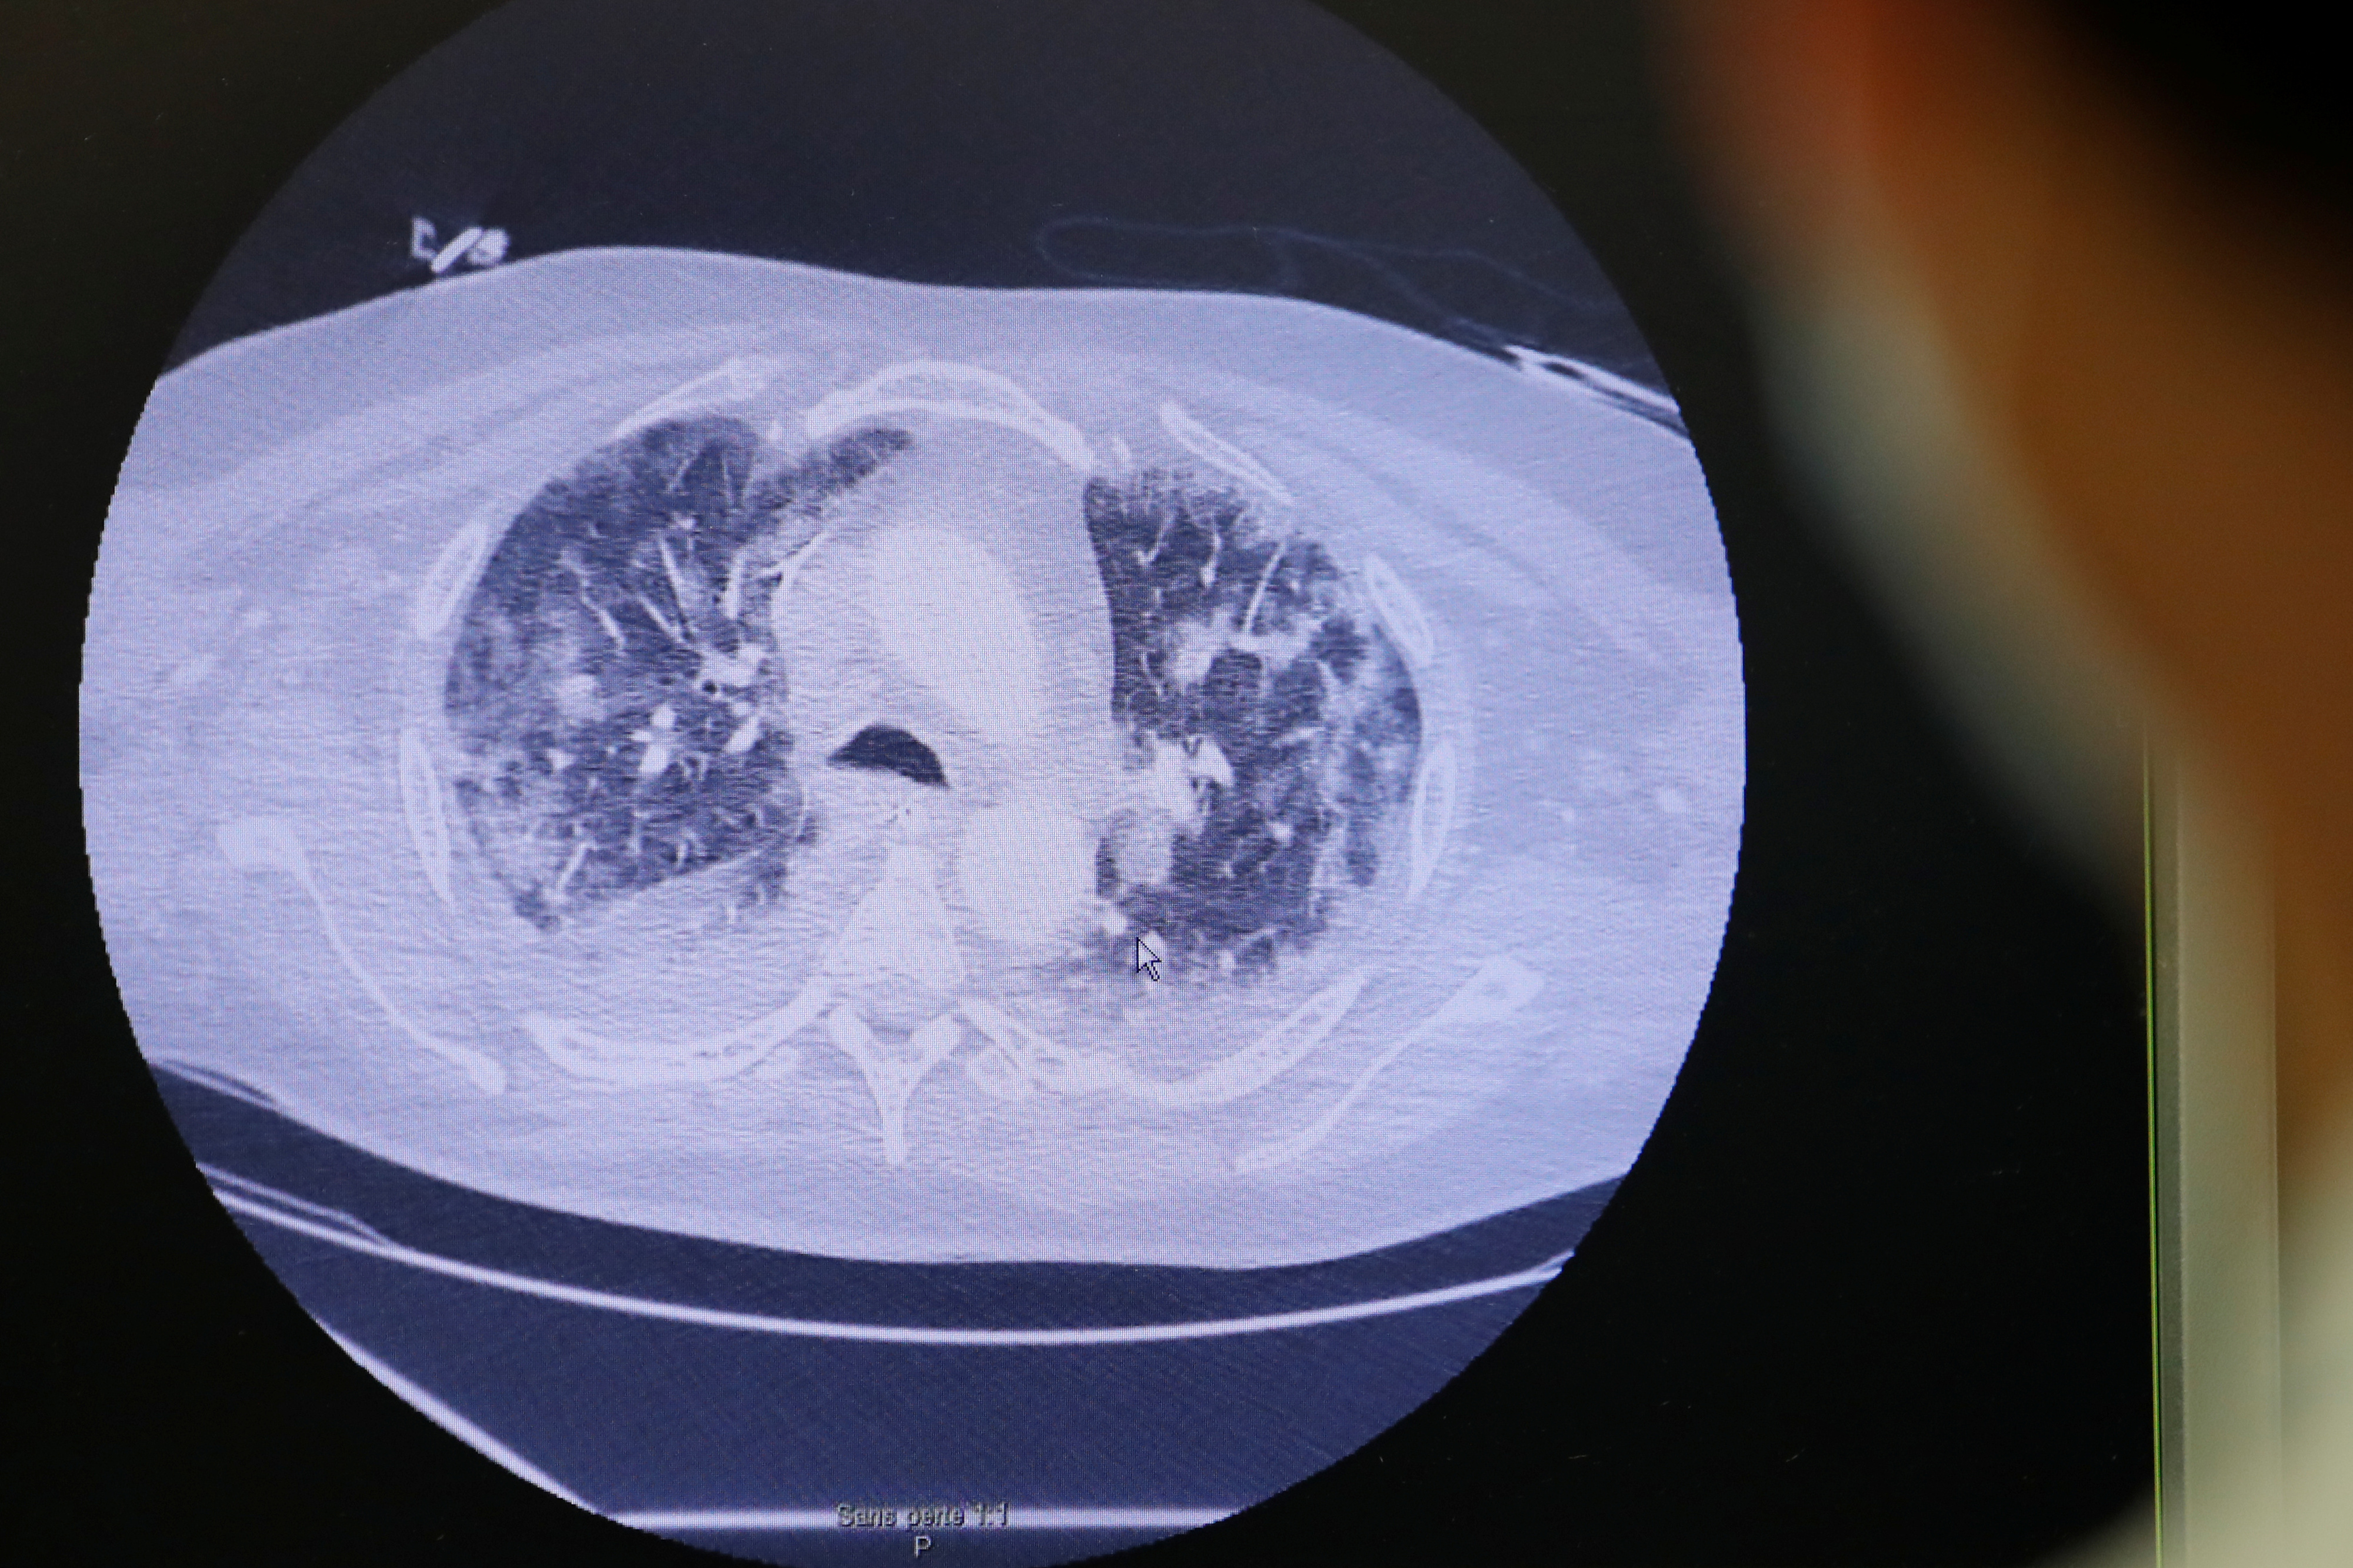

Das Coronavirus greift die Lunge an.